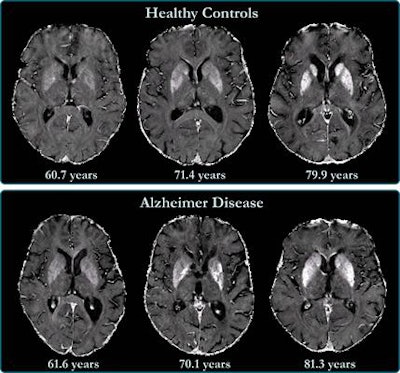

R2* maps of healthy control participants and participants with Alzheimer disease. R2* maps are windowed between 10 and 50 sec-1. Images courtesy of the RSNA.The study found higher iron deposits in the Alzheimer's patients' deep gray matter, total neocortex, and in the temporal and occipital lobes compared to healthy controls.